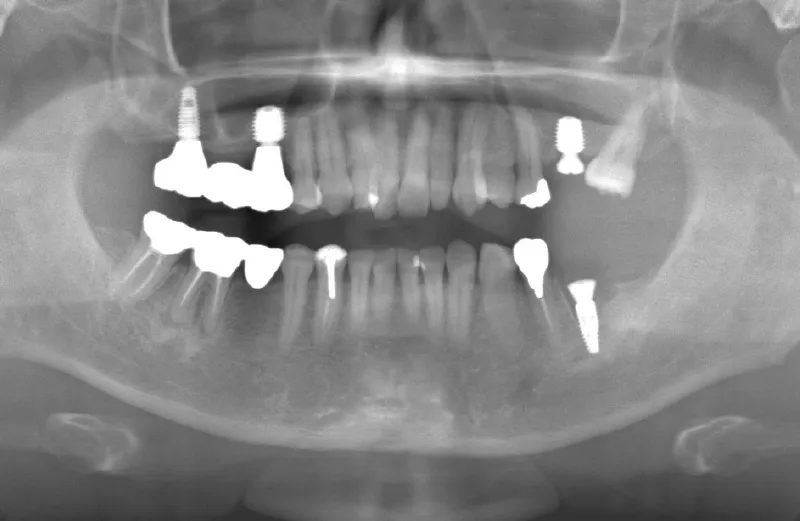

メガジェンオペ症例

メガジェンオペの症例紹介01

治療前

治療後

| 主訴 | 上入れ歯は以前に入れたことがあるが違和感が強く入れられなかったのでインプラントで治療して欲しい。 他院では上顎洞までの垂直骨量が1~3mm程度しかないのでサイナスリフトが必須であり、インプラント治療で歯が入るまでに1年以上かかると言われたのでセカンドオピニオンを希望で来院。 |

|---|---|

| 治療期間 | 2.5ヶ月で仮歯が入り、 4ヶ月で最終補綴物が入って終了。 |

| 費用 | 約1,500,000円 |

| 治療内容 | エクストラワイドショートインプラントを埋入し、上顎洞を移植材を用いずに挙上しインプラントを埋入した。約2.5ヶ月で仮歯を装着し、様々な機能面に問題がないことを確認し4ヶ月で最終補綴物を装着して終了した。 |

| 治療のリスク | インプラント埋入オペ時に術者が上顎洞内にインプラントを迷入させる可能性がある。これは術者が技術的に熟練していれば防ぐことが可能。 |